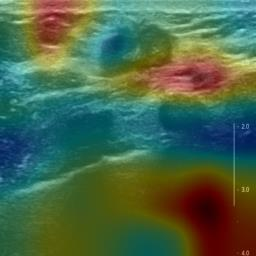

Ultrasonography is an important routine examination for breast cancer diagnosis, due to its non-invasive, radiation-free and low-cost properties. However, it is still not the first-line screening test for breast cancer due to its inherent limitations. It would be a tremendous success if we can precisely diagnose breast cancer by breast ultrasound images (BUS). Many learning-based computer-aided diagnostic methods have been proposed to achieve breast cancer diagnosis/lesion classification. However, most of them require a pre-define ROI and then classify the lesion inside the ROI. Conventional classification backbones, such as VGG16 and ResNet50, can achieve promising classification results with no ROI requirement. But these models lack interpretability, thus restricting their use in clinical practice. In this study, we propose a novel ROI-free model for breast cancer diagnosis in ultrasound images with interpretable feature representations. We leverage the anatomical prior knowledge that malignant and benign tumors have different spatial relationships between different tissue layers, and propose a HoVer-Transformer to formulate this prior knowledge. The proposed HoVer-Trans block extracts the inter- and intra-layer spatial information horizontally and vertically. We conduct and release an open dataset GDPH&GYFYY for breast cancer diagnosis in BUS. The proposed model is evaluated in three datasets by comparing with four CNN-based models and two vision transformer models via a five-fold cross validation. It achieves state-of-the-art classification performance with the best model interpretability.